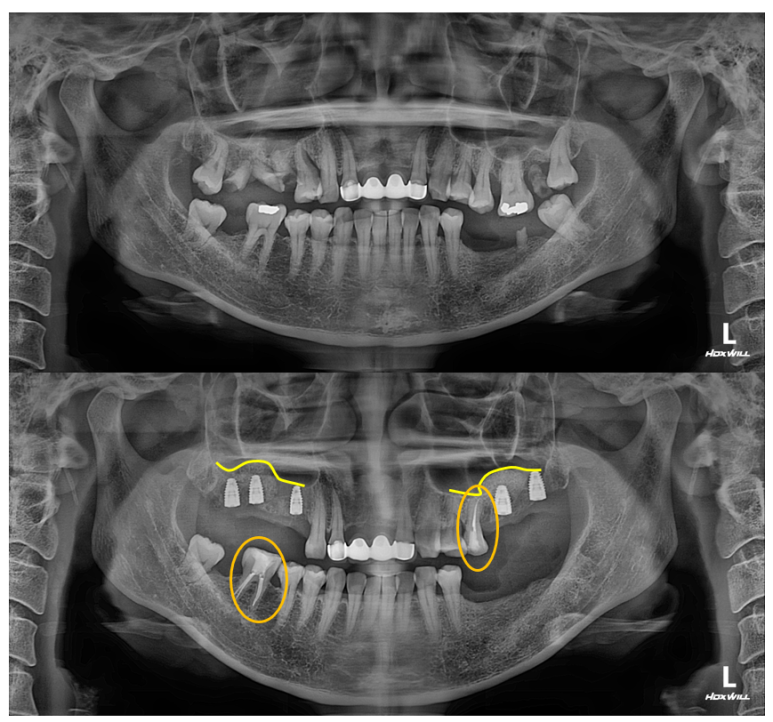

대부분의 수술은 위턱부터 시작합니다.

상악동 뼈이식술을 하면서 임플란트 수술을 시행하였습니다.

왼쪽 위 어금니에 2개, 오른쪽 위 어금니에 3개 총 다섯개의 스트라우만 임플란트를 사용하였습니다.

제 포스팅을 많이 보신 분들은 아실텐데, 상악동 뼈이식술도 함께 진행하였습니다.

내원했을 당시 처음과 비교해보면, 노란선으로 표시된 상악동 뼈이식술 라인을 관찰하실 수 있을겁니다.

상당히 깔끔하게 수술이 이뤄졌네요!

그리고 저희 치과는 치과보존과 전문의 원장님이 함께 계신데, 주황색으로 표시된 두 치아가 깔끔하게 신경치료가 마무리 된 것을 보실 수 있습니다.

깔끔하게 신경치료가 마무리 되면, 보다 조화로운 '교합평면'을 만들어낼 수 있죠.

위턱 임플란트를 심어드리고 3주 뒤에 아래턱 임플란트를 심었습니다.

보통 환자분들이 한 번에 수술을 다 하면 너무 힘들어하시기 때문에, 위와 아래로 수술을 나누어 하게 되는데요.

통상적으로 위턱 뼈가 밀도가 낮아 치유 기간을 한달정도 더 가져가기 때문에 수술은 위턱 수술 먼저 완성 후 아래턱 수술 순서로 진행됩니다.

오른쪽 아래 어금니에 2개, 왼쪽 아래 어금니에 1개 (그리고 사랑니 발치까지) 수술이 잘 이루어졌네요!!

위턱은 상악동 골이식술이 있어 수술시간 1시간 안팎, 아래턱은 30분 안팎 걸렸던 것 같습니다.